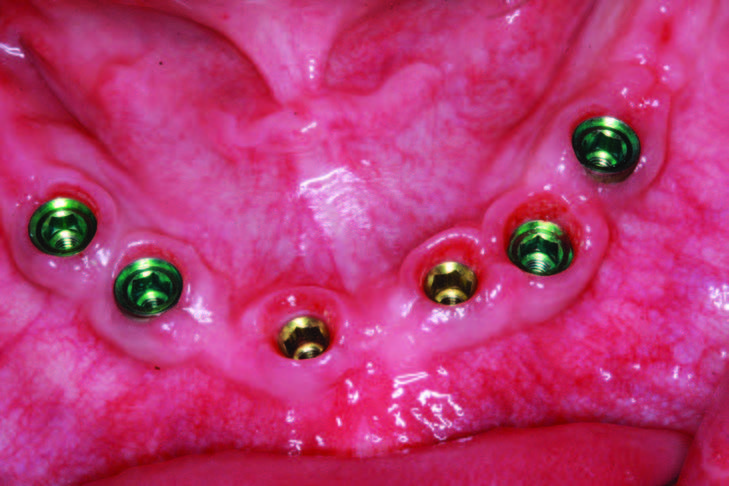

At the time of edentulation, the mandibular implants were placed. The Tapered Internal Implant System (BioHorizons) has Laser-Lok technology, or micro-grooves that allow the implant to be placed subcrestal, equicrestal, or supracrestal to hold on to the bone and hemi-desmosomes of the tissue. The buttress threads provide for aggressive cutting, progressive bone loading, and excellent bone-implant contact, while the 1.5-mm deep internal hex provides a stable seal of prosthetic components. Implant placement was performed according to CBCT analysis. After placement, the lip of bone on the lingual was removed with the Piezosurgery by Mectron. The flat side of BioHorizons’ 3inOne abutment was oriented toward the labial for ease in orientation after uncovering and for impressions where a ball top screw can be used with this abutment as an impression transfer coping (Figure 7). After 4 months of healing and the uncovery of the permucosal healing abutments, the soft tissue was healthy and had great keratinized tissue (Figure 8a). The preliminary impression allowed the lab team (Glidewell Dental Laboratory) to return a verification jig to assess the accuracy of the impression and to ensure that the prosthesis would seat passively. The Sheffield one-screw test was performed after luting the verification jig together with Primatec Pattern Resin (Figures 8b and 8c). This resin has less than 0.1% shrinkage, making it the luting option of choice when compared to other types of luting resins. Once the jig was luted, alternate screws were loosened, and the terminal screws were also loosened to verify the jig would not lift up. A master impression (Aquasil Ultra Xtra [Dentsply Sirona]) was taken over the verification jig. This impression material provides an extended set time of 5 minutes to allow for adequate time to load the tray, inject around abutments, and find the screw access channels using the open tray impression technique.

The maxillary arch surgery began after the mandibular arch had healed. The full maxillary edentulation was also done using Piezosurgery and Physics Forceps. As seen in Figure 9, the lingual beak and labial bumper atraumatically “lift” the tooth out of the socket while maintaining the buccal plate. If sectioning of the tooth is required, or if purchase points need to be created for the forceps beak, then this forceps technique can allow for efficient root removal. After the extractions, the sockets were grafted with LifeNetHealth bone (Salvin Dental Specialties), and Mem-Lok type I collagen fiber membranes (BioHorizons) were used over the grafted maxilla due to the need to maintain graft coverage for 26 to 38 weeks. This material was also chosen because of its macromolecular pore size and its easy adaptation to the surgical site. After healing for 4 months, the maxillary implants were virtually planned using a new CBCT scan that first scanned the denture in with fiduciary markers (Suremark) placed and then the denture was scanned separately. This dual scan protocol (as directed by 3DDX) permits deluxe reformatting so that implants can be planned with the upper denture in a separate color, allowing for proper 3-D placement of implants within the confines of the approved occlusal construct (Figure 10). After fine-tuning services, a mucosal- born surgical guide was fabricated with maxillary implants placed for the most optimal A-P spread. The guide tubes, stabilization pins, and quality control were done by 3DDX (Figure 11). The bilateral subantral sinus augmentation was not done in order to accommodate the grandparents’ budget. The maxillary arch was grafted, and an immediate denture was delivered.